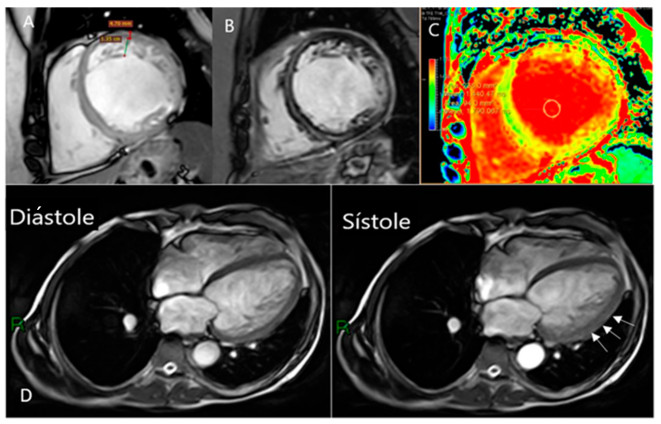

Secuencias diagnósticas de RMC. A: Imagen cine con secuencia SSFP, en eje corto a nivel medio del corazón, donde se observa la trabeculación ventricular con la medición de las dos capas del miocardio, presentando criterios de MNC (4,7/1,35=3,48) B: Secuencia de doble inversión recovery, con Gadolinio en análisis tardío, donde se puede observar hiperintensidad intramiocárdica lineal, a nivel del septum interventricular y pericárdica lateral. C: Secuencia de mapping miocárdico, con aumento del T1 a nivel septal, de 1440 ms, en un paciente con miocarditis repetitivas. D: Paciente con miocardiopatía dilatada y deterioro severo de la función ventricular. Imagen de la izquierda en diástole y a la derecha en sístole. Durante la sístole, se puede observar mejor motilidad miocárdica en los segmentos con MNC en la cara lateral (flechas) en comparación con los segmentos septales “sin MNC”.

4. La tercera parte de la definición considera la presencia de “…síntomas y signos característicos…” Al MNC se lo ha asociado a arritmias cardíacas, accidente cerebrovascular e insuficiencia cardíaca, con signos y síntomas característicos de estas patologías. Del total de 140 pacientes de nuestra población, solamente el 21% presentó una FEVI menor al 55%; la gran mayoría de los pacientes con MNC (el 79%), no tenían deterioro de la función ventricular izquierda (Tabla 1). Al comparar los pacientes con FEVI normal, con los pacientes con FEVI deprimida, no se observaron diferencias con relación a la magnitud del MNC, ni en la relación de miocardio compacto/no compacto (Tabla 2). Por lo tanto, la magnitud del MNC, no se puede asociar en forma directa con la disfunción ventricular. Es interesante marcar acá algunas dudas con respecto a los pacientes con deterioro de la función ventricular y MNC. Nosotros hemos observado, que las alteraciones más importantes en la motilidad de la pared regional del ventrículo izquierdo ocurren en las regiones “sin MNC” como puede observarse en pacientes con insuficiencia cardíaca y acinesia severa en las regiones septales o basales del ventrículo izquierdo, cuando el MNC comprometía la cara anterolateral y apical (Figura 2-C). Esto iría en contra de la afirmación de que el MNC es la causa primaria de disfunción ventricular en estos pacientes.